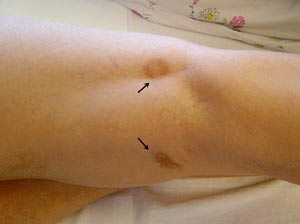

Etter oppholdet var pasienten i dårlig form, med betydelig asteni og økende dyspné ved moderat anstrengelse. Hun oppdaget også et par blåmerker på høyre underekstremitet, og var til utredning hos hudlege. Det ble tatt hudbiopsi, som ikke førte til noen nærmere diagnose.

Ved innleggelsen var blodtrykket 120/80 mm Hg og pulsen 70, regelmessig. Det var ingen halsvenestuvning eller deklive ødemer, og det var normale funn ved auskultasjon av hjerte og lunger. Hun var palpasjonsøm under høyre kostalbue, men leveren var ikke sikkert forstørret. Det ble funnet tre ca. 2 x 3 cm store ekkymoser på høyre underekstremitet (fig 1).

Pasienten hadde altså i lang tid vært slapp og hatt økende dyspné. I tillegg hadde hun en uklar febertilstand som hadde vart i ca. én uke. Klinisk undersøkelse, bakteriologiske prøver og røntgen thorax påviste ikke noe sikkert infeksjonsfokus. Hun kunne selvfølgelig ha hatt en gastroenteritt, ettersom hun var plaget med diaré, oppkast og feber og hadde moderat forhøyet CRP. Funn av ekkymoser i høyre underekstremitet gav imidlertid mistanke om endokarditt med perifer embolisering av vegetasjoner fra klaffeapparatet. Det ble derfor utført ekkokardiografi.